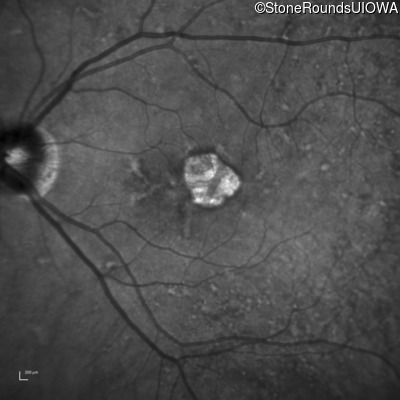

Infrared Fundus Photograph - Left - 20/40 +1

Exemplar